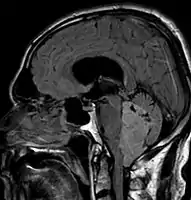

Micrograph of a myxopapillary ependymoma. HPS stain. Ependymoma of 4.ventricle in MRI.

Ependymoma of 4.ventricle in MRI. Ependymoma of 4.ventricle in MRI.

Ependymoma of 4.ventricle in MRI. Ependymoma of 4.ventricle in MRI. Left without, right with contrast-enhancement.

Ependymoma of 4.ventricle in MRI. Left without, right with contrast-enhancement.